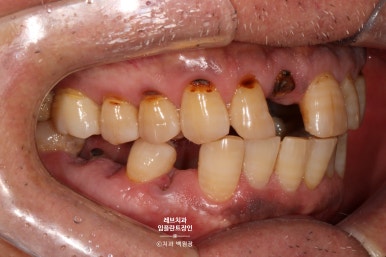

보시면 가만히 있어도 치아와 잇몸 사이에서 고름이 올라오는 것을 보실 수 있어요..

흡연을 좋아하시던 분이었고, 만성 치주염이 심해져서 치주농양까지 진행된 상태입니다.

치과용 파노라마 사진에서도 왼쪽 위 송곳니 주변으로 잇몸뼈가 사라진 것을 보실 수 있는데요,

확대해볼 수 있는 치근단 방사선 사진을 보시면, 송곳니 뿌리 주변으로 거무딩딩하게 뼈가 없어진 것을 보실 수 있습니다.

만성치주염으로 상당히 많은 양의 잇몸뼈가 파괴되었죠.